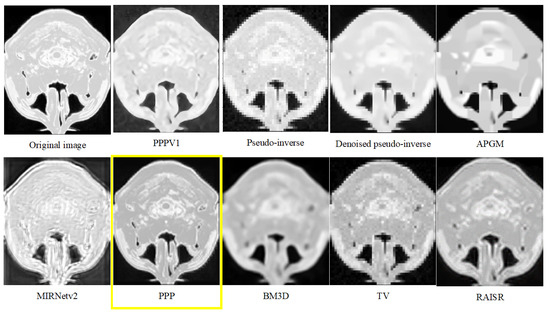

| Dataset 1 | Dataset 2 | |||

|---|---|---|---|---|

| Average | St.Dev | Average | St.Dev | |

| PPPV1 | 22.49 | 0.44 | 25.26 | 0.25 |

| Pseudo-inverse | 19.52 | 0.56 | 22.81 | 0.26 |

| Denoised pseudo-inverse | 20.36 | 0.51 | 23.73 | 0.28 |

| APGM | 19.91 | 0.34 | 23.78 | 0.22 |

| MIRNetv2 | 14.05 | 0.27 | 14.26 | 0.18 |

| PPP | 26.59 | 0.49 | 25.67 | 0.65 |

| BM3D | 20.58 | 0.82 | 23.72 | 0.36 |

| TV | 22.48 | 0.44 | 23.50 | 0.29 |

| RAISR | 21.99 | 0.43 | 25.77 | 0.32 |

| PPPV1 | 6.14 | 0.15 | 6.66 | 0.17 |

| PPP | 5.82 | 0.15 | 6.39 | 0.16 |

| Pseudo-inverse | 14.13 | 0.36 | 14.08 | 0.35 |

| Denoised pseudo-inverse | 14.13 | 0.36 | 14.08 | 0.35 |

| APGM | 13.86 | 0.35 | 13.03 | 0.33 |

| BM3D | 10.66 | 0.27 | 11.92 | 0.30 |

| TV | 12.22 | 0.31 | 12.82 | 0.32 |

| RAISR | 5.87 | 0.15 | 9.61 | 0.24 |

| MIRNetv2 | 7.18 | 0.18 | 7.95 | 0.20 |